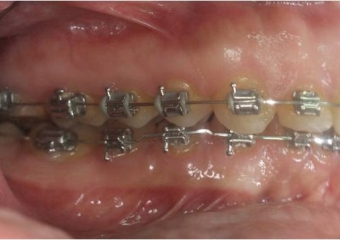

Mordida final